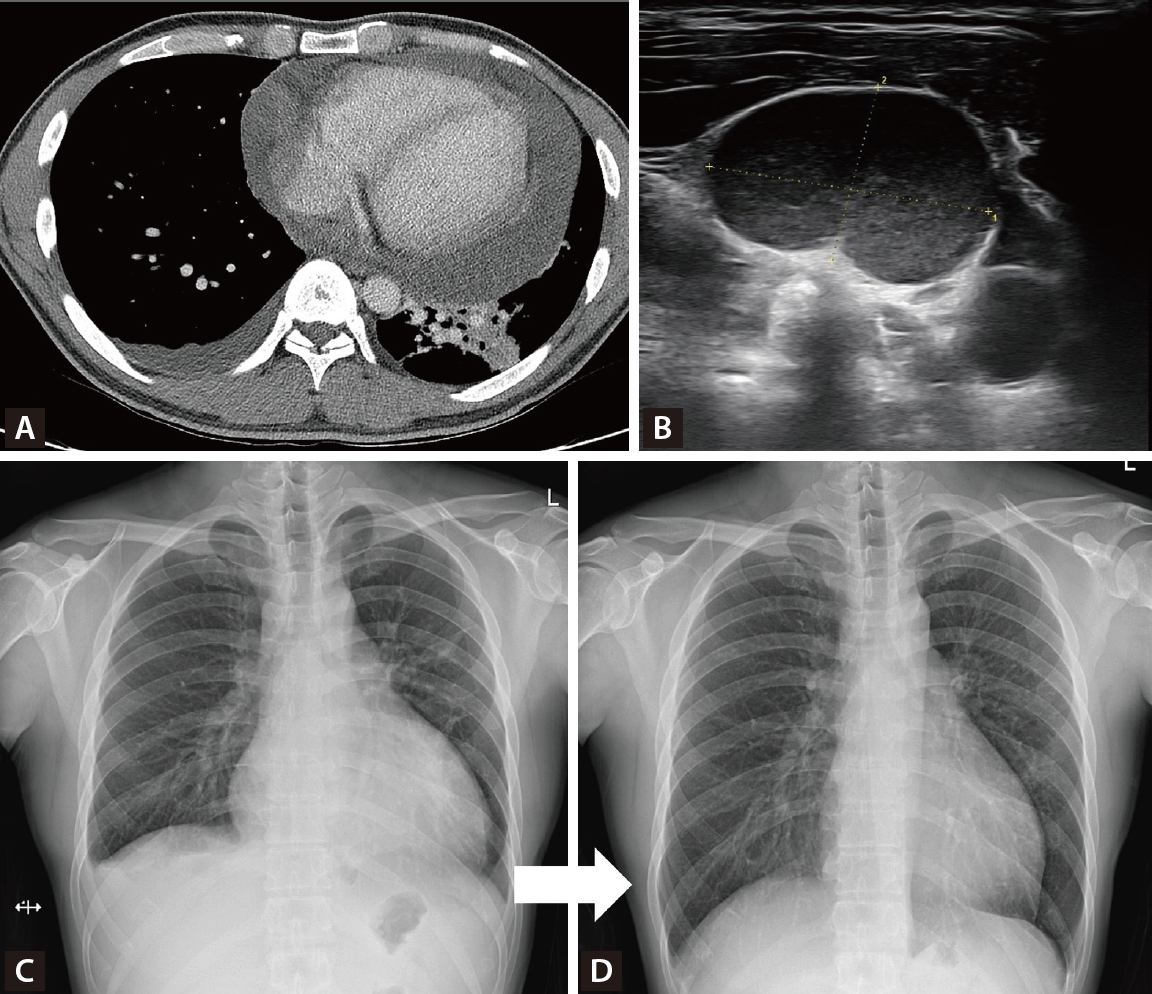

However, the patient developed persistent cough, dyspnea, and shortness of breath over one month, showing no improvement with conventional management, along with several palpable cervical lymph nodes. Chest computed tomography revealed a large pericardial effusion with impending tamponade physiology and diffuse parenchymal infiltration in the left lung field (Fig. 2A). Ultrasound-guided biopsy of the cervical lymph nodes revealed granulomatous inflammation with necrosis (Fig. 2B). Pericardiocentesis drainage was performed, showing positive AFB with M. tuberculosis culture, and adenosine deaminase (ADA) 11.3 IU/L, which was compatible with tuberculous pericarditis, and IGRA result were positive. Standard anti-tuberculosis medication (HREZ) was initiated for six months with rapid symptom improvement (Fig. 2C, D).

(A) Chest computed tomography findings. On axial view, massive pericardial effusion with left lower lung infiltration were seen. (B) Neck ultrasound findings. About 2.1 cm-sized enlarged lymph node was seen. (C) Initial X-ray findings. Cardiomegaly due to pericardial effusion and pleural effusion were seen. (D) Follow-up X-ray findings. One month after pericardiocentesis, pericardial effusion was completely disappeared.